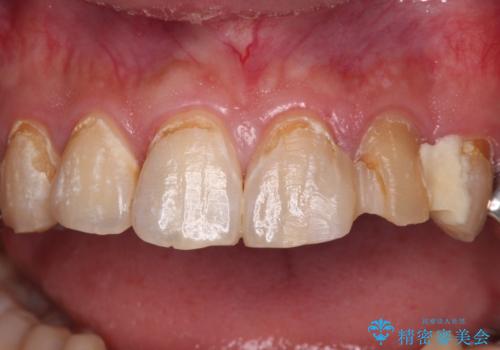

- むし歯の影響で、前歯を見せることが恥ずかしいとのことで来院された患者様です。

全顎的にむし歯が多く、治療が必要な歯はたくさんありましたが、まずは非常に目立つ前歯から処置を行うこととしました。

むし歯は歯肉内にまで進行していると外科処置が必要となりますが、ギリギリの位置でとどまっていたため、速やかにオールセラミッククラウンにて補綴治療することとしました。